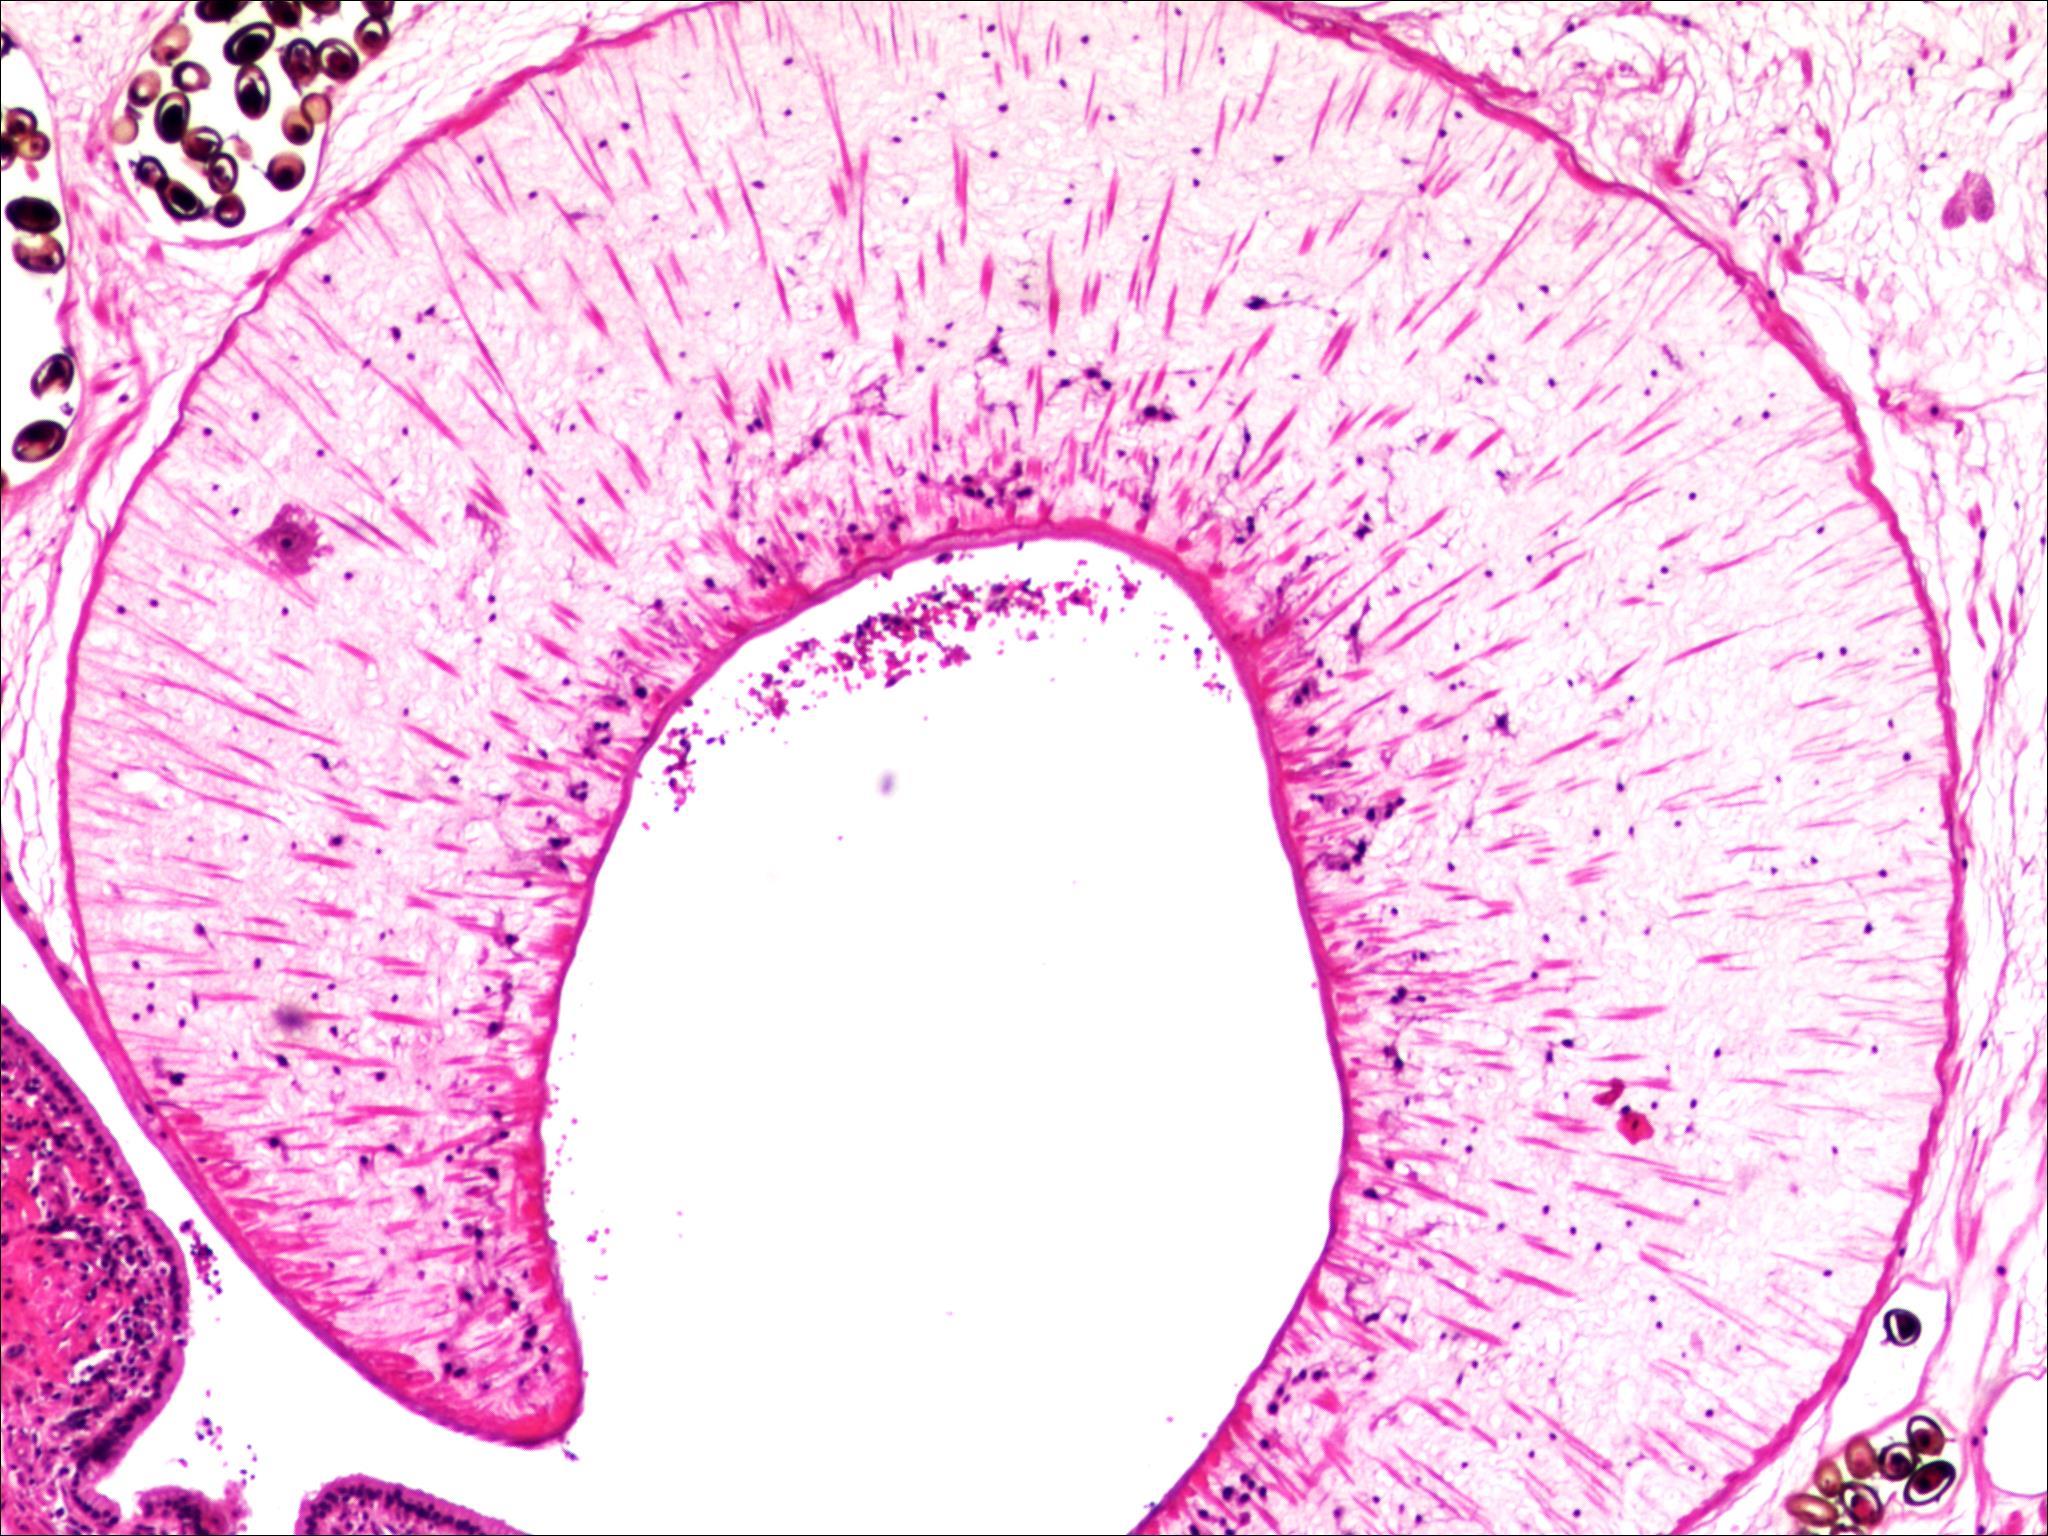

摘要:背景与目的 复发性急性胰腺炎(RAP)病因复杂,其中由寄生虫感染引起者极为罕见。胰腺阔盘吸虫侵入胰管导致梗阻并诱发RAP,目前国内尚无报道。本研究通过1例确诊病例,结合文献复习,探讨其临床特征、诊断难点及防治要点。方法 回顾分析湖南师范大学附属第一医院2023年收治的1例胰腺阔盘吸虫致RAP患者的临床资料,包括影像学、手术及病理学结果,并综述国内外相关文献。结果 患者为59岁女性,表现为反复上腹痛4年。影像学提示胰体尾部多囊性病变并胰管扩张,术前被考虑为胰管内乳头状黏液性肿瘤。行腹腔镜胰体尾及脾切除术后,病理证实导管内存在吸虫虫体及虫卵,最终确诊为胰腺阔盘吸虫感染。术后恢复良好,随访1年未再发胰腺炎。结论 胰腺阔盘吸虫是RAP罕见的病因,临床及影像学表现缺乏特异性,易误诊为胰腺囊性肿瘤。对于病因不明的RAP,尤其是有食用生食或野味史的患者,应重视寄生虫学检查,如粪便虫卵及血清抗体检测,以早期确诊并指导治疗。